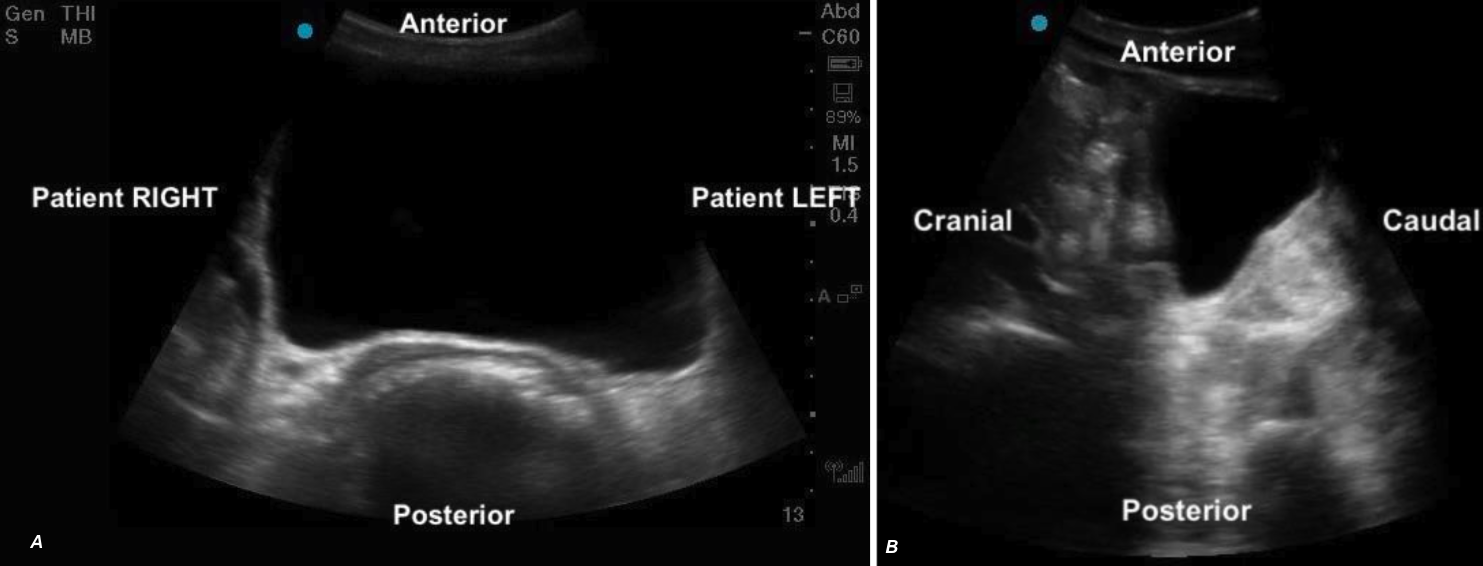

Subxiphoid Four Chamber

The subxiphoid 4 chamber view is particularly well suited for RV assessment due to the anterior position of the RV and the ability to use the liver as an acoustic window. This view provides excellent visualization of the RV free wall and is especially useful for evaluating RV free wall motion, wall thickness, RV size and global function.

Figure 17. Normal subxiphoid 4 chamber view labeled

What is Normal?

• Triangular shape

• Thin walled

• Smaller than the LV: A general rule of thumb is that the RV should be ~2/3 the size of the LV [19].

• The RV should squeeze inwards uniformly, with the free wall moving toward the septum during systole.

Figure 18: Subxiphoid 4 chamber view demonstrating normal RV size and function